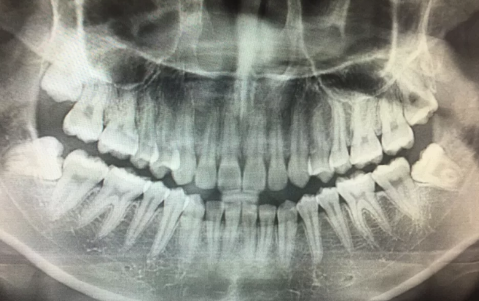

牙医建议拔掉智齿主要是因为牙齿反复发炎,会影响邻近的牙齿。

1、反复炎症:智齿出牙不完整,龈冠覆盖后侧部分形成冠周袋。不注意个人卫生,局部软组织往往会发炎,出现疼痛症状,所以需要拔掉智齿才能有效改善。

2、影响邻近牙齿:如果牙齿生长位置不正确而拥挤,就有可能对邻近牙齿造成损害,使咀嚼功能严重受损,因此需要拔除智齿。